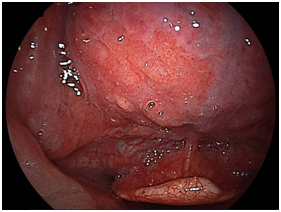

Suction, irrigation, and insufflation are all possible with this trans-nasal flexible endoscope, which facilitates the clinical assessment of this particular area. The tip of the endoscope can make a U-turn up to an angle of 210°. We previously reported the usefulness of the intra-oropharyngeal U turn method.7‒8 We were able to observe all areas of the tongue from the base (Figure 2A) to the apex (Figure 2B) and a frontal view of the papillae vallatae was obtained in all patients. The squamous cell carcinoma of the base of the tongue detected by EG-L580NW is shown in Figures 3A (white light imaging) and 3B (LCI). After completing the intra-oropharyngeal U-turn method, the tip of the endoscope is inserted gently between the epiglottis and the tongue to observe the vallecula and the tonsil side of the epiglottis.

Figure 3A Superficial squamous cell carcinoma of the base of the tongue with white-light imaging.

We detected 11 cases of superficial squamous cell carcinoma of the base of the tongue between April 2012 and March 2016. All the patients were complicated with current (n=3) or previous (n=8) esophageal squamous cell carcinoma. The patient characteristics are shown in Table 1. The mean age of the patients was 63.7years (range, 49-73years), and all patients were male. Four cases were diagnosed using trans-nasal endoscopy with the FICE system, seven cases were diagnosed using trans-nasal endoscopy with the LASERIO system. The average time to complete a thorough examination for one patient was approximately from 1 to 2minutes, regardless of the presence of abnormal findings. Biopsy specimen were obtained in all patients, and diagnosed as squamous cell carcinoma pathologically. Table 2 shows the treatment results. Five lesions were flat type (Figure 4A), four were elevated (Figure 4B), and two were depressed (Figure 4C). Regarding the tumor size, eight were T1, three were T2. No lymph node metastasis was detected in any case. Six cases were treated by endoscopic laryngo-pharygeal surgery,15 and 3 cases were treated by chemo-radiotherapy. One case was followed because of esophageal cancer. One case was treated by trans-oral robotic surgery at another hospital. For the seven resected specimens, the median tumor thickness was 800μm (range, 250-3000μm), and the median tumor diameter was 11mm (range, 10-25mm). Histologically, two of these lesions were squamous cell carcinoma in situ, five showed microinvasion of the subepithelial tissue. During a median follow-up period of 26months (range,11-56months), 1 patient, which patient’s tumor thickness was 3000μm, developed lymph node metastasis, which was treated by neck lymphadenectomy and chemo-radiotherapy. Three of the 11 patients cases were died of another disease, and 8 were alive as drafting this manuscript.

Figure 4A Flat type

Macroscopic types of superficial squamous cell carcinoma of the base of the tongue.

Figure 4B Elevated type.

Figure 4C Depressed type.